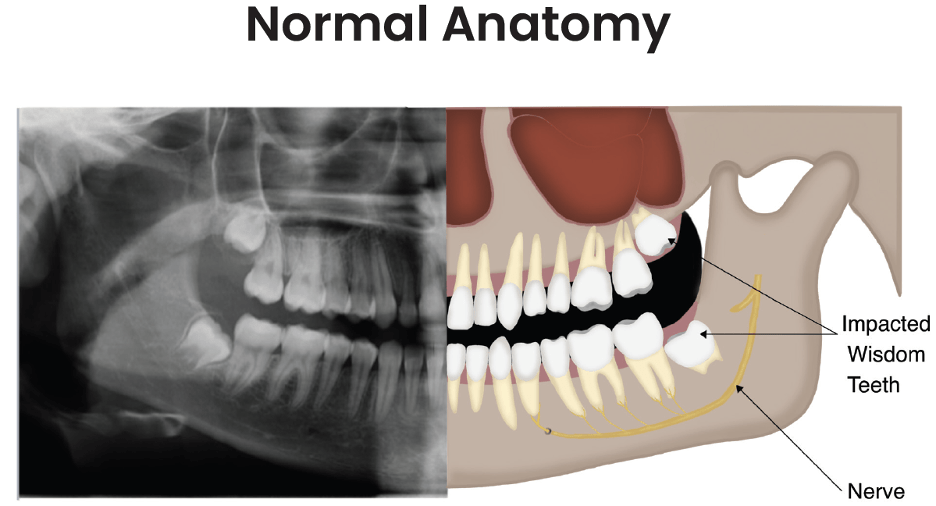

impacted wisdom teeth symptoms treatment dentique dental clinic